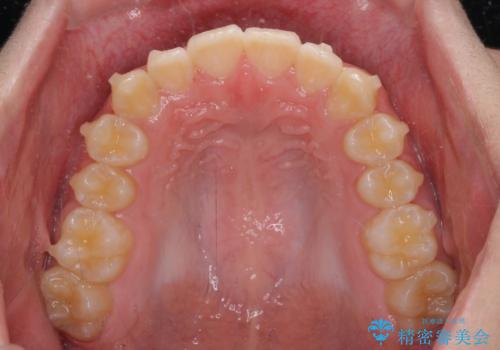

しっかり使って短期間で治療 インビザラインによる叢生解消

- 上下前歯のデコボコを気にして来院された患者様です。

「しっかりと装着する」が実行でき、高校3年生の秋には治療を終えることができました。